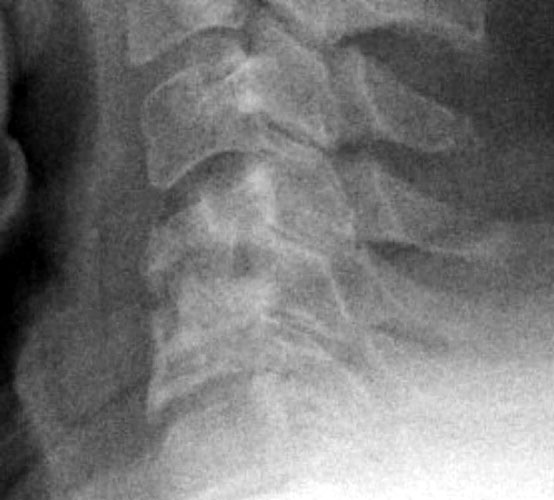

8 months later, the follow-up films demonstrate lucency at the graft site worrisome for resorption. Figure _. Axial CT examination, without contrast.